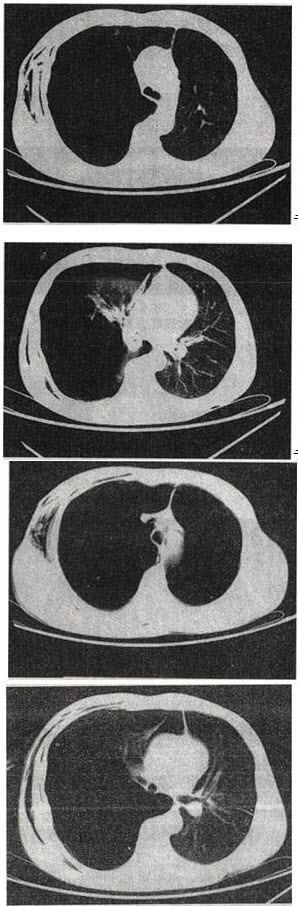

- 单项选择题 患者男,32岁,被车撞伤后1小时急诊行CT检查。结合图像,最可能的诊断为()。

A、右侧气胸

B、右肺不张

C、右侧气胸并皮下纵隔气肿

D、右侧肺大疱并皮下纵隔气肿

E、支气管断裂

- C